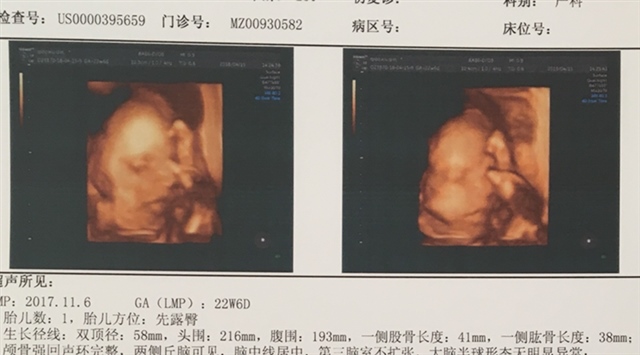

怀孕 孕29周+4天